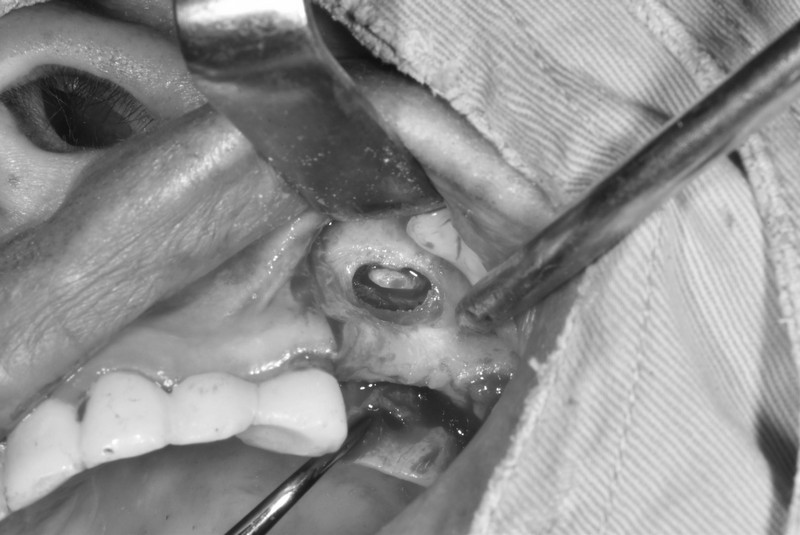

鼻竇增高術

針對上顎後牙缺牙區骨量不足的患者,將上顎竇膜輕柔抬升並填補骨粉,以增加骨高度,為植牙提供穩固支撐與長期穩定性。